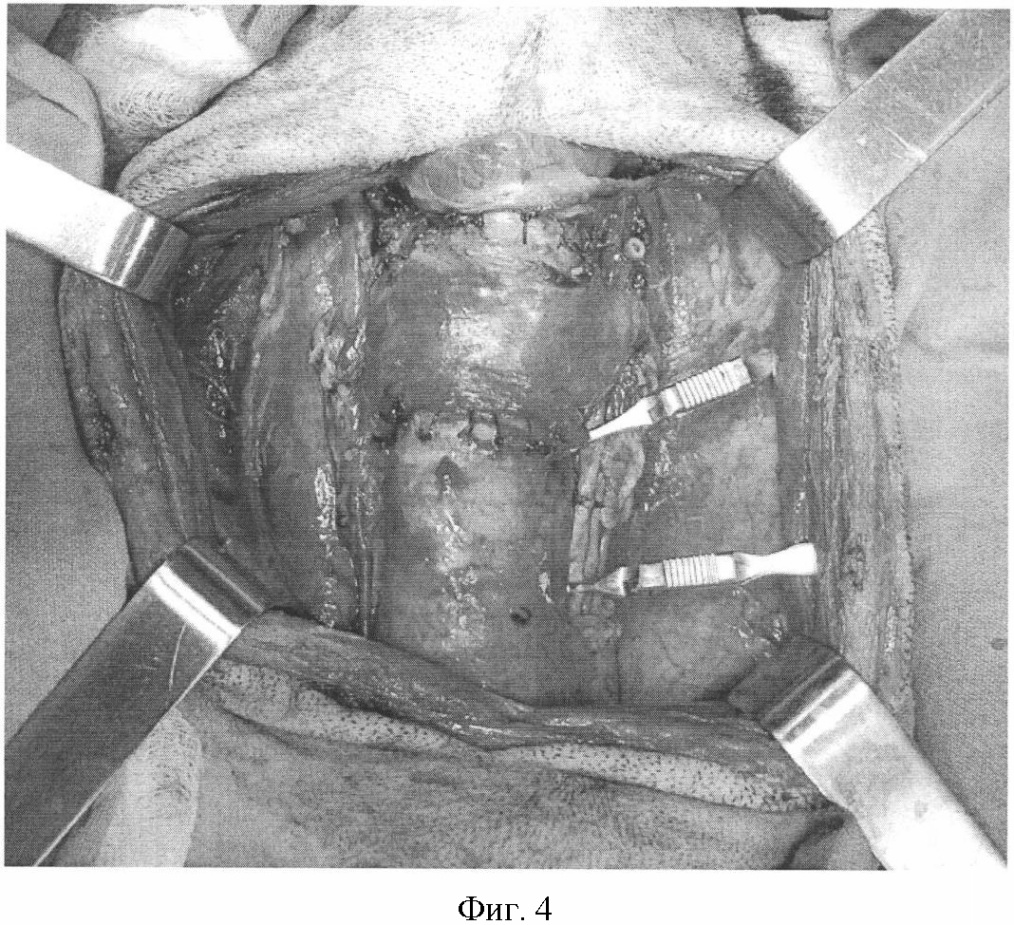

Фиг.4. Реперфузия тиреотрахеального комплекса путем пуска кровотока правой сонной артерии, наложены ларинготрахеальный и трахеотрахеальный анастомозы, иссечен сосудистый протез, наложен анастомоз между иссеченным участком левой сонной артерии и центральным концом оставшейся левой сонной артерии.